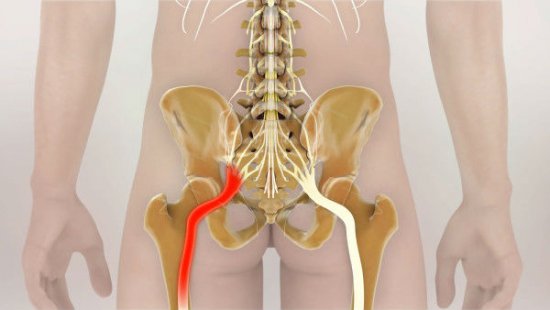

Еще один источник болей в пояснице – наличие межпозвонковых грыж. При их ущемлении, сдавливании нервных корешков возникает довольно сильная, резкая боль, справиться с которой на начальных стадиях помогают стероидные и нестероидные противовоспалительные препараты.

Грыжа позвоночника – частая причина боли

Признаком неблагоприятного исхода является люмбалгия, которая проявляется спектром разнообразных симптомов. Боли по ходу нервного корешка могут отдавать в ягодицы и ступни. Дискомфорт появляется при наклонах (даже при наклоне головы вниз), смехе, кашле и т. д. Болевой синдром усиливается при поднятии лежа на спине прямой ноги.